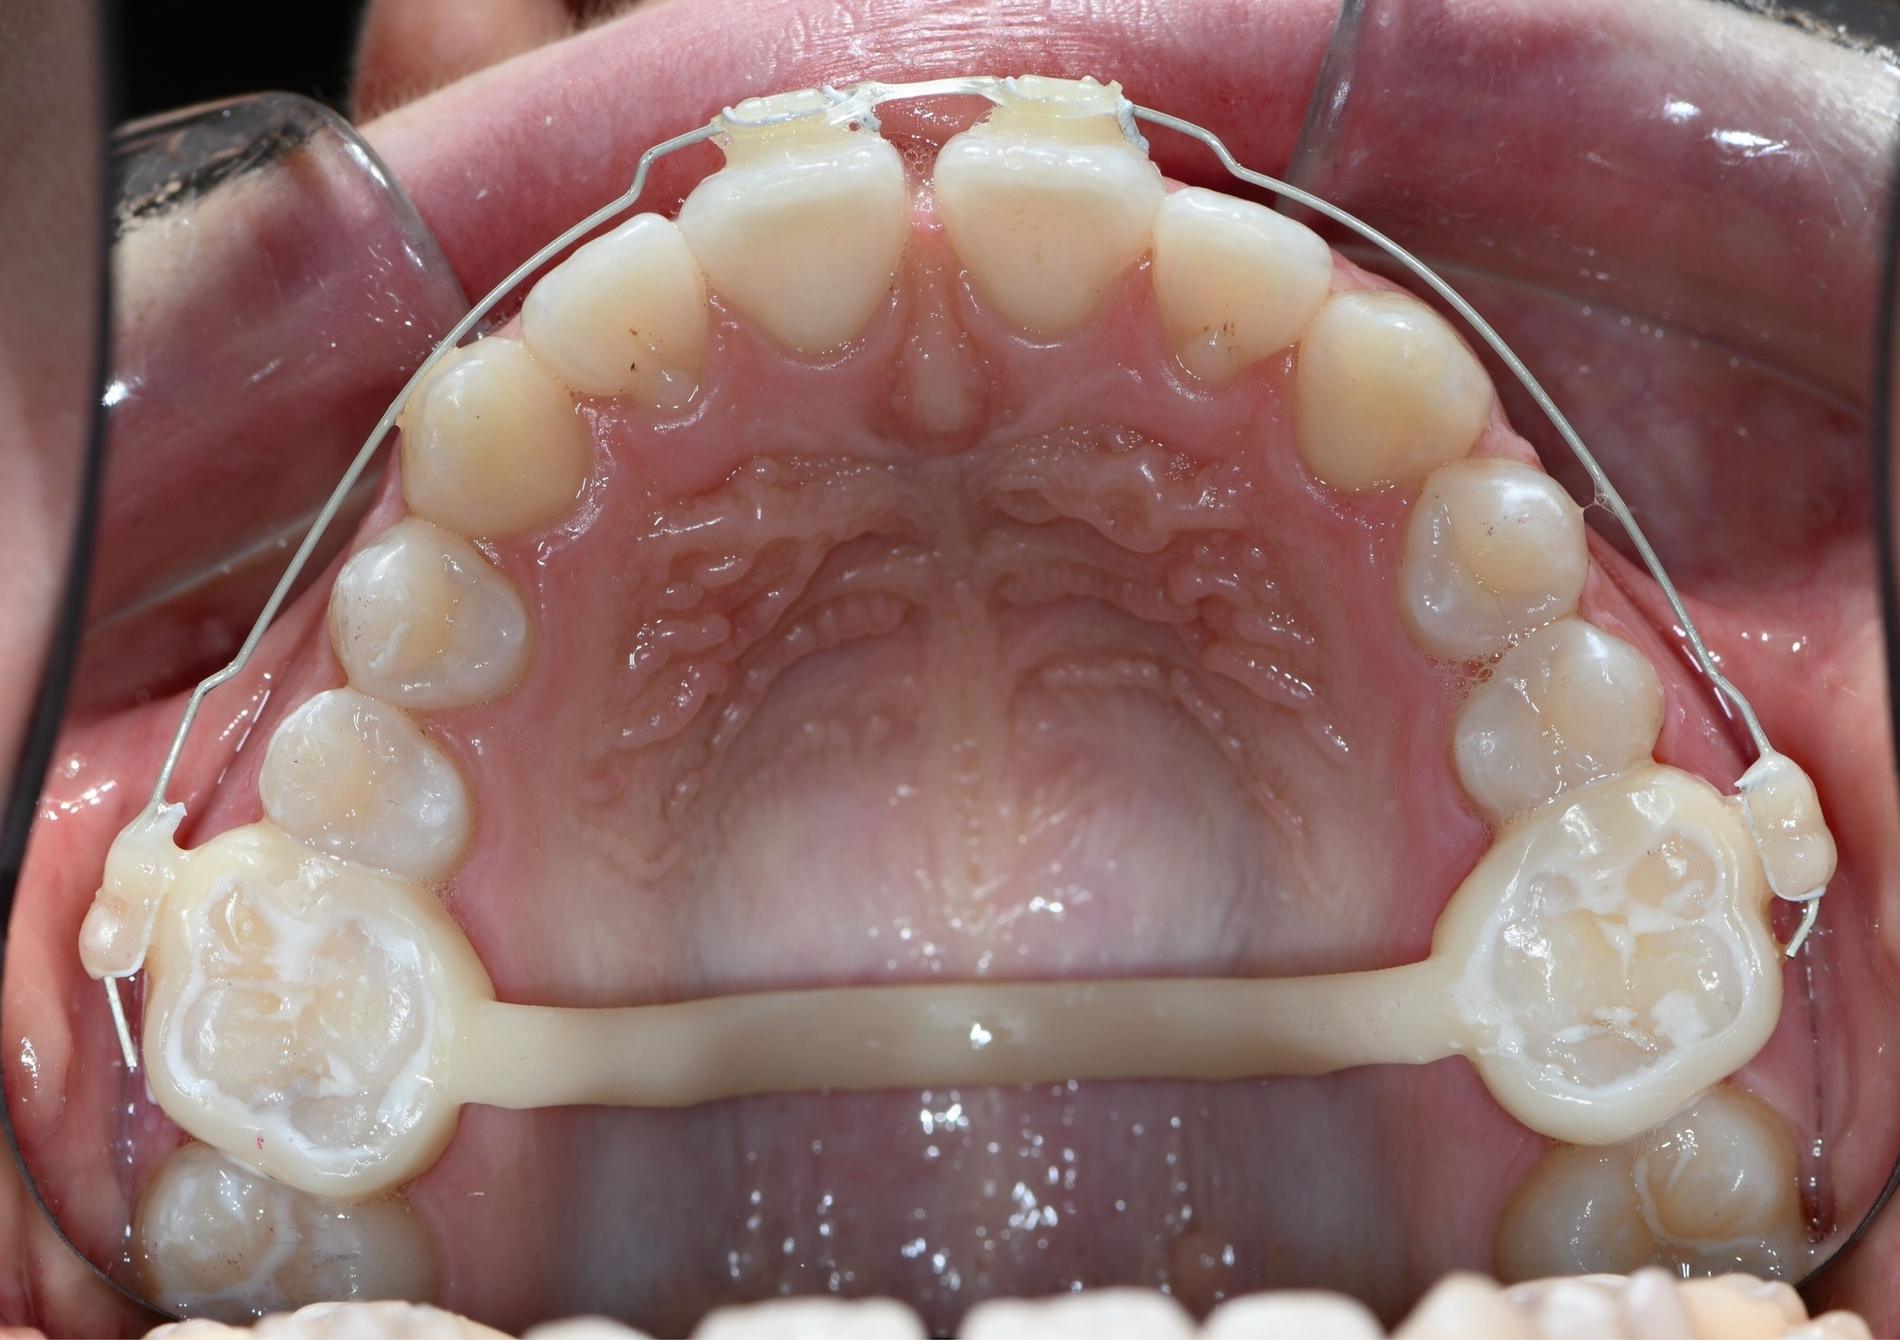

Auch die Herstellung zusätzlicher Elemente, wie beispielsweise Transpalatinalbögen aus Keramik-gefüllten 3-D-Druckkunststoffen, ist möglich (Abbildung 2c) [Thurzo et al., 2022], muss jedoch in großangelegten Studien noch auf eine ausreichende klinische Suffizienz untersucht werden. Weiter bieten 3-D-gedruckte Transferguides die Möglichkeit des „Indirekten Klebens“ [Deahl et al., 2007; Bozelli et al., 2013; Li et al., 2019; Sabbagh et al., 2022], wobei die Bracketpositionierung bereits vor dem Einsatz digital festgelegt und schließlich durch den Transferguide intraoral übertragen wird (Abbildung 2d). Neben einer verkürzten Stuhlzeit erlaubt dieses Verfahren eine besonders hohe Genauigkeit der Bracketpositionierung.